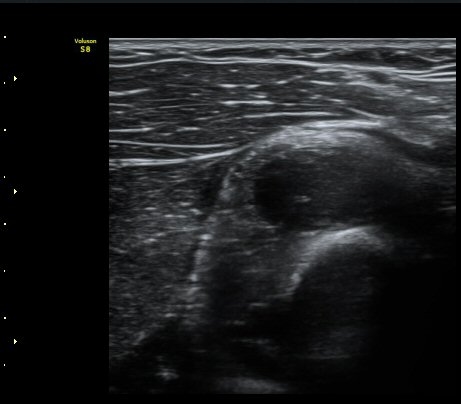

ŽÃËÀÚ¸¦ Á» ´õ ¸»´ÜÀ¸·Î À̵¿ÇÏ´Ï ³¶Á¾Àº ´õ Å©°Ô °üÂûµÈ´Ù(±×¸² 3, 4).